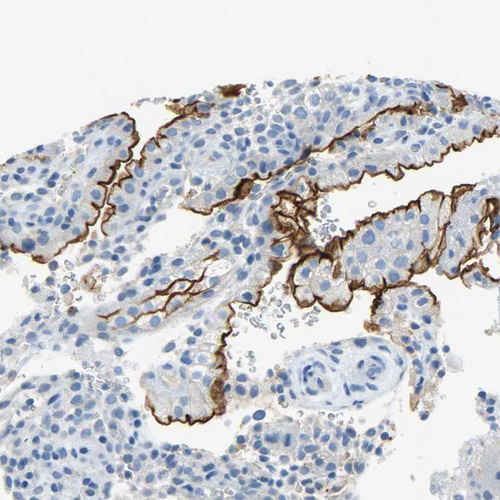

Immunohistochemistry analysis in human placenta and skeletal muscle tissues using HPA004922 antibody. Corresponding PROM1 RNA-seq data are presented for the same tissues.